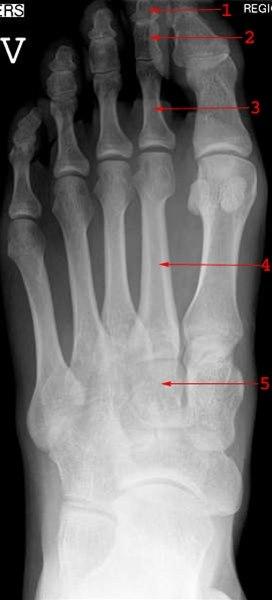

Foten består av totalt 26 bein. I bakfoten finnes hælbeinet (calcaneus) og ankelbeinet (talus). I midtfoten finnes båtbeinet (naviculare), kube-beinet (cuboideum) og tre såkalte cuneiforme-bein. Fremfoten består av fem mellomfotsbein (metatarser) og 14 tåbein (falanger). Rørknokler som metatarser og falanger har en bakre (proksimal) og en fremre (distal) ende. Den midtre delen av rørknoklene er smal og lang (skaftet), og de ytre delene er fortykkede. Den proksimale enden kalles basis, og den distale benevnes caput. Se tegninger nedenfor:

Røntgen bekrefter diagnosen. Brudd i fotens metatarser og falanger kan være vanskelige å påvise hos barn på grunn av de mange vokstsentrene. I slike tilfeller er det nødvendig å sammenligne med bilder av den andre foten. Annen bildediagnostikk kan noen ganger være nødvendig, eks. scintigrafi, CT, MR, ultralyd.